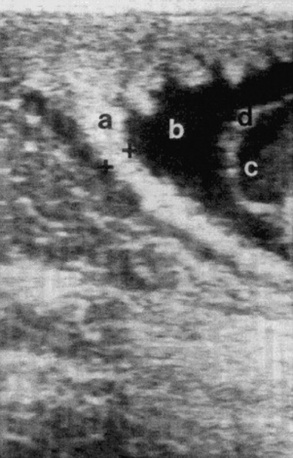

image

Fig. 43-8 Transrectal imaging of the combined thickness of the uterus and the placenta (CTUP). Measurements of the CTUP (distance between + and +) were recorded from the ventral part of the uterine body, close to the cervix. a, Placenta adjacent to the cervix; b, allantoic fluid; c, amniotic fluid; d, the amnion.

Modified from Renaudin CD, Troedsson MH, Gillis CL, et al: Ultrasonographic evaluation of the equine placenta by transrectal and transabdominal approach in the normal pregnant mare, Theriogenology, 47:559, 1997.